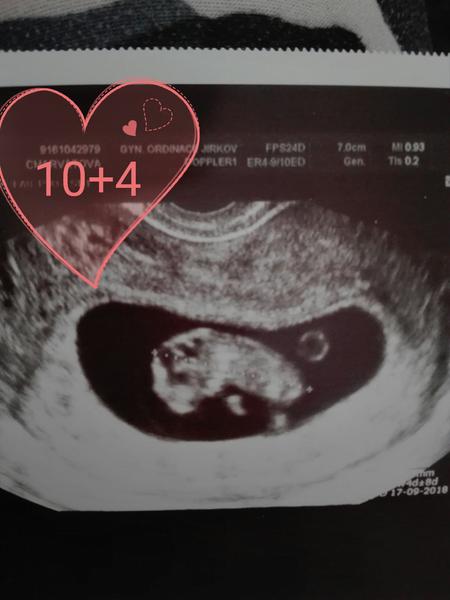

Tak u me potvrzené tehotenstvi dnes sem 10dpo

Wow 10dpo? A už je to tak krásně vidět? Tak to já jsem asi min

Tohle je starsi foto 13.3budu mit dalsi